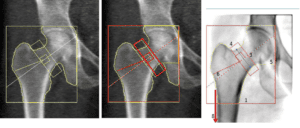

Comparison of image quality between clinical and retail scans

Accuracy in measurement is also critical. For hip scans, it is essential that the neck of the femur is measured at the narrowest part [4]. Retail scans often fail to accurately identify and measure this specific area.